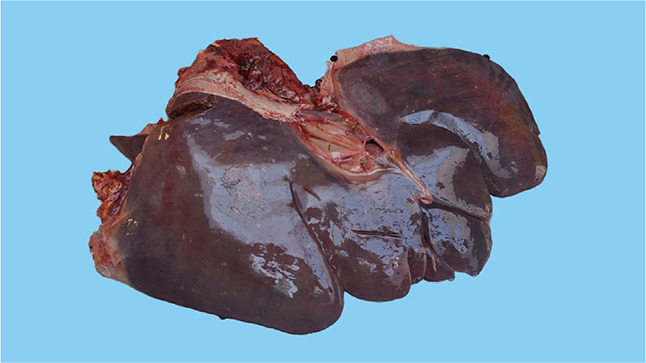

本研究描述了一匹马的吡咯里西啶生物碱中毒病例。据作者所知,这是首例确诊的蛇莓中毒病例。一匹 6 岁、体重 450 千克的爱尔兰驹母马因出现肝性脑病症状而被送往布尔诺兽医大学(捷克)马科诊所,尽管接受了强化治疗,但病情仍随时间推移而逐渐恶化,最终导致安乐死。本文介绍了一种复杂的诊断和治疗方法,包括死后病理解剖学和组织病理学检查。在肝脏组织病理学方面,肝脏坏死并伴有出血、脂肪变化和炎症。随后对放牧区进行的检查发现了木豚草(Senecio ovatus)的存在。采用灵敏的色谱法测定了血浆和肝脏中的吡咯烷生物碱及其代谢物。在两个样本中都检测到了吡咯里西啶生物碱的代谢物。虽然证明了吡咯里西啶生物碱中毒,但却没有这种疾病的典型组织病理学结果。从我们的病例中可以清楚地看出,吡咯里西啶类生物碱中毒病例的组织病理学检查并不总是确凿无疑的。

This study describes a case of poisoning by pyrrolizidine alkaloids in a horse. To the best of the author's knowledge, this is the first confirmed case of Senecio ovatus poisoning. A six-year-old 450-kg Irish cob mare was presented to the Equine Clinic of the University of Veterinary Sciences Brno (Czechia) with symptoms of hepatic encephalopathy, which progressively worsened with time despite intensive therapy and led to euthanasia. A complex diagnostic and therapeutic approach including the post-mortem patoanatomical and histopathological examination is described here. Regarding the histopathology of the liver, there was necrosis with haemorrhage, fatty changes and inflammation. A later inspection of the grazing area revealed the presence of Senecio ovatus (wood ragwort). A sensitive chromatographic method was used to determine the pyrrolizidine alkaloids and their metabolites in the plasma and the liver. In both of the samples, metabolites of pyrrolizidine alkaloids were detected. Although pyrrolizidine alkaloid poisoning was proven, the histopathological findings typical for this disease were absent. It is clear from our case that the histopathology in cases of poisoning by pyrrolizidine alkaloids may not always be conclusive.